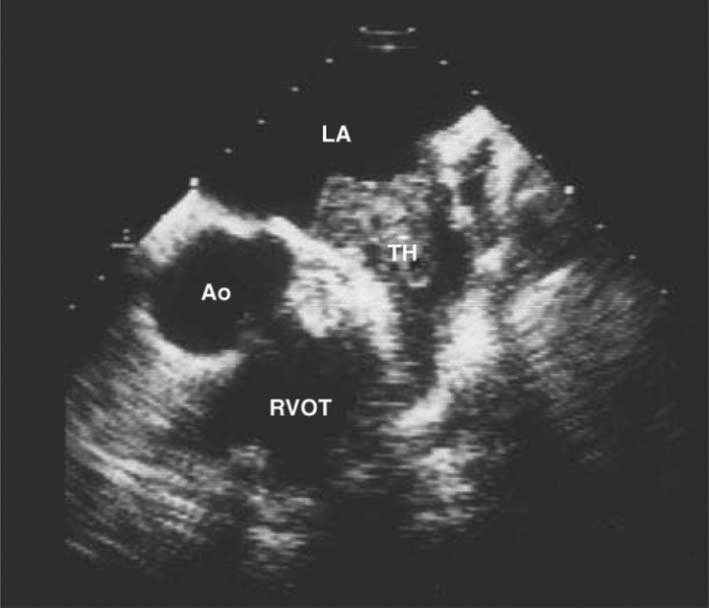

![]() |

الشكل (8) خثرة في لسينة الأُذين الأيسر كما يبدو بالصدى عبر المريء عند مريض لديه صمة دماغية وتضيق في الصمام التاجي حيث لا يكشف الصدى المجرى عبر جدار الصدر وجود هذه الخثرة وتكشف بإجراء الصدى عبر المريء. TH = الخثرة، LA = الأُذين الأيسر، Ao = الأبهر، RVOT = مخرج البُطَين الأيمن. |